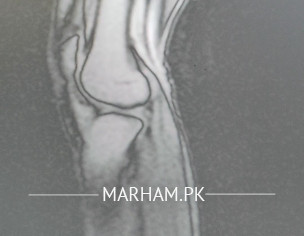

Meri exercise ki doran knee injury hogie bones wagera sab thek lagg rhy walk kar leta ho sahy si lkn tez run nae kar sakta aor jump bhe nae kar pa rha MRI images attach kar rha kindly guide kare kya issues hai meri knee me

MRI me LCL diagnose howy ha or lateral meniscus tear physiotherapy chal rhy hai lkn uss ka khas farq nae ha aor injury ko 9 months howy hai jo ki sports Injury thi leg twist hone ki wajha si daily life me walk wagera bilkul normal hoty hai lkn running aor jumping me pain hota hai ab kya suggestions ha kindly guide kejoye

there are only 5 images

grossly it seems OK

more details about injury and symptoms is required to help you better